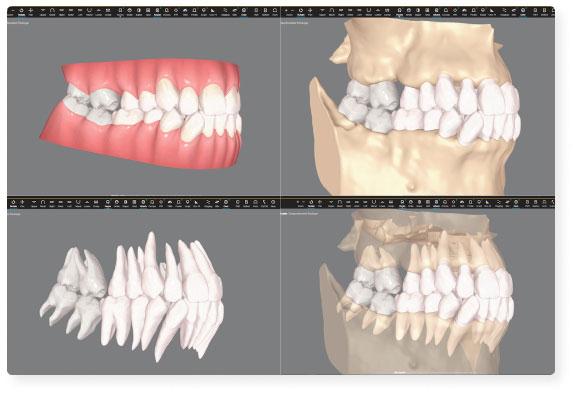

- 3D skenēšana un radiogrāfija nodrošina detalizētus attēlus par zobiem, žokļiem un apkārtējiem audiem.

- Datortomogrāfija (CT) sniedz trīsdimensiju attēlus, kas nepieciešami sarežģītām procedūrām, piemēram, implantācijai vai sakņu kanālu ārstēšanai.

- 3D zobu skenēšana;

- Digitālā zobu modelēšana.